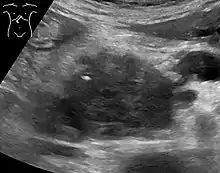

Abdominal ultrasonography of pancreatic cancer (presumably adenocarcinoma), with a dilated pancreatic duct to the right.

Medical imaging techniques, such as computed tomography (CT scan) and endoscopic ultrasound (EUS) are used both to confirm the diagnosis and to help decide whether the tumor can be surgically removed (its "resectability").[12] On contrast CT scan, pancreatic cancer typically shows a gradually increasing radiocontrast uptake, rather than a fast washout as seen in a normal pancreas or a delayed washout as seen in chronic pancreatitis.[56] Magnetic resonance imaging and positron emission tomography may also be used,[2] and magnetic resonance cholangiopancreatography may be useful in some cases.[32] Abdominal ultrasound is less sensitive and will miss small tumors, but can identify cancers that have spread to the liver and build-up of fluid in the peritoneal cavity (ascites).[12] It may be used for a quick and cheap first examination before other techniques.[57]